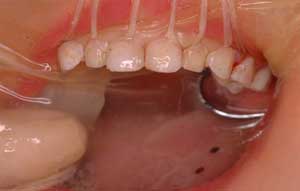

| 子どもの前歯でも |

進行止めのためのサホライドを塗ると

こんな風に黒くなります。

ごく表面の虫歯は茶色くなります。

虫歯部分を取り除き、レジンで治すと

きれいになります。

ラバーダム下なら安全で確実にできます。

3歳でも、前歯がきれいな方が私は好きです。 |